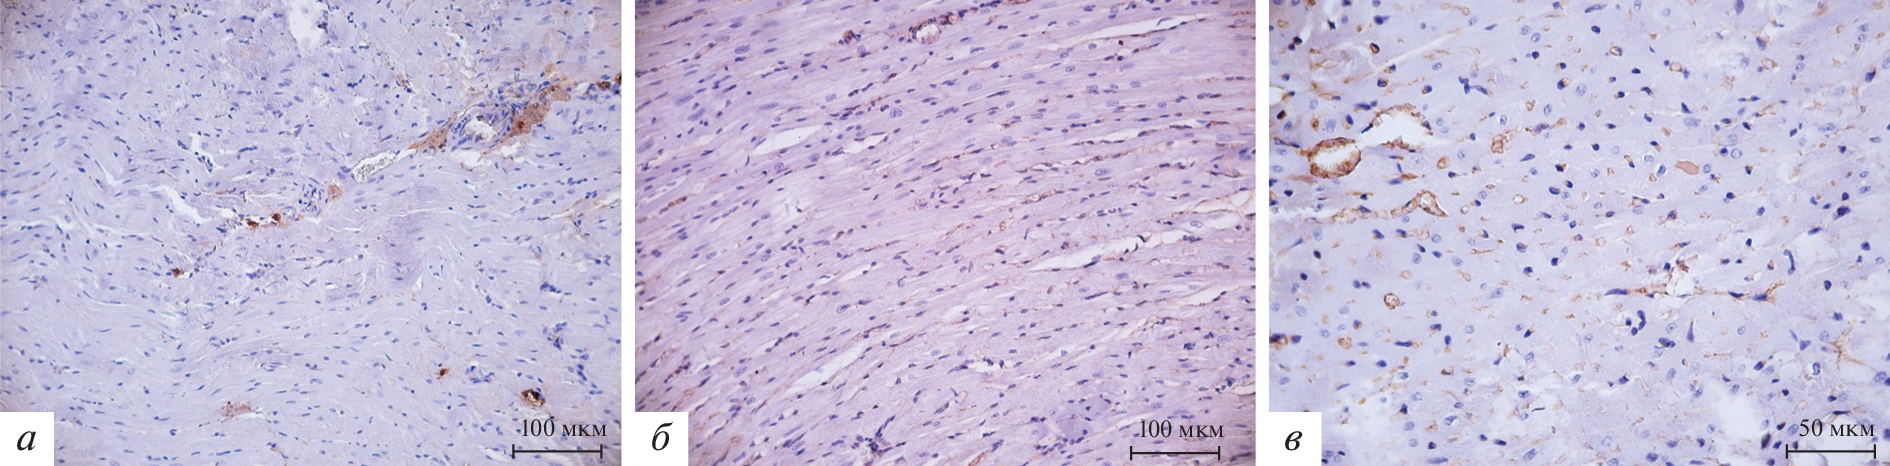

Immunohistochemical detection of matrix metalloproteinases (MMP) 2 and 9 was carried out in the myocardium of the left ventricle of prematurely born (21 and 21.5 days of gestation) and full-term (22 days of gestation) rats at 42, 56 and 180 days of the postnatal period of ontogenesis. The intensity of immunopositive staining was assessed by a scoring system. Preterm birth leads to an increase in the intensity of the immunopositive reaction to MMP-2 and MMP-9 in the wall of the left ventricle of rats. An increase in the intensity of the MMP-2 positive reaction in the left ventricle of rats is observed the earlier, the greater the degree of prematurity. The intensity of the MMP-9 positive reaction in the left ventricle of male rats is greater with a more pronounced degree of prematurity. An increase in the intensity of the MMP-2 and MMP-9 positive reaction in the wall of the left ventricle of female rats due to preterm birth is determined exclusively in animals born on the 21st day of pregnancy, that is, with a greater degree of prematurity.